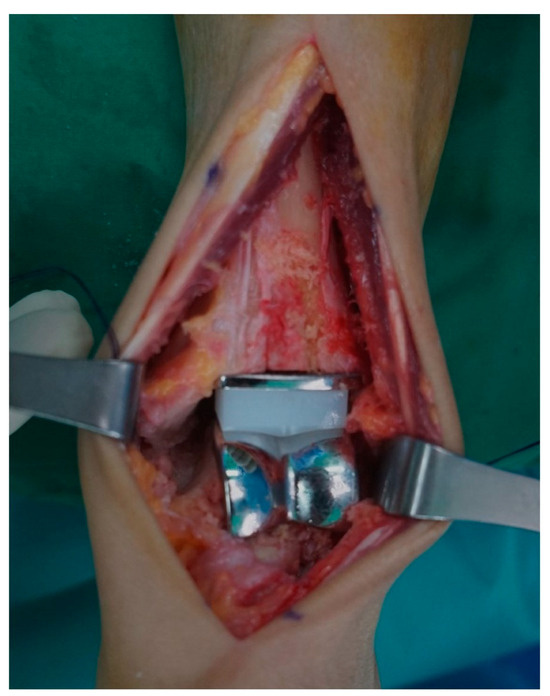

2.5. Postoperative Wound Assessment